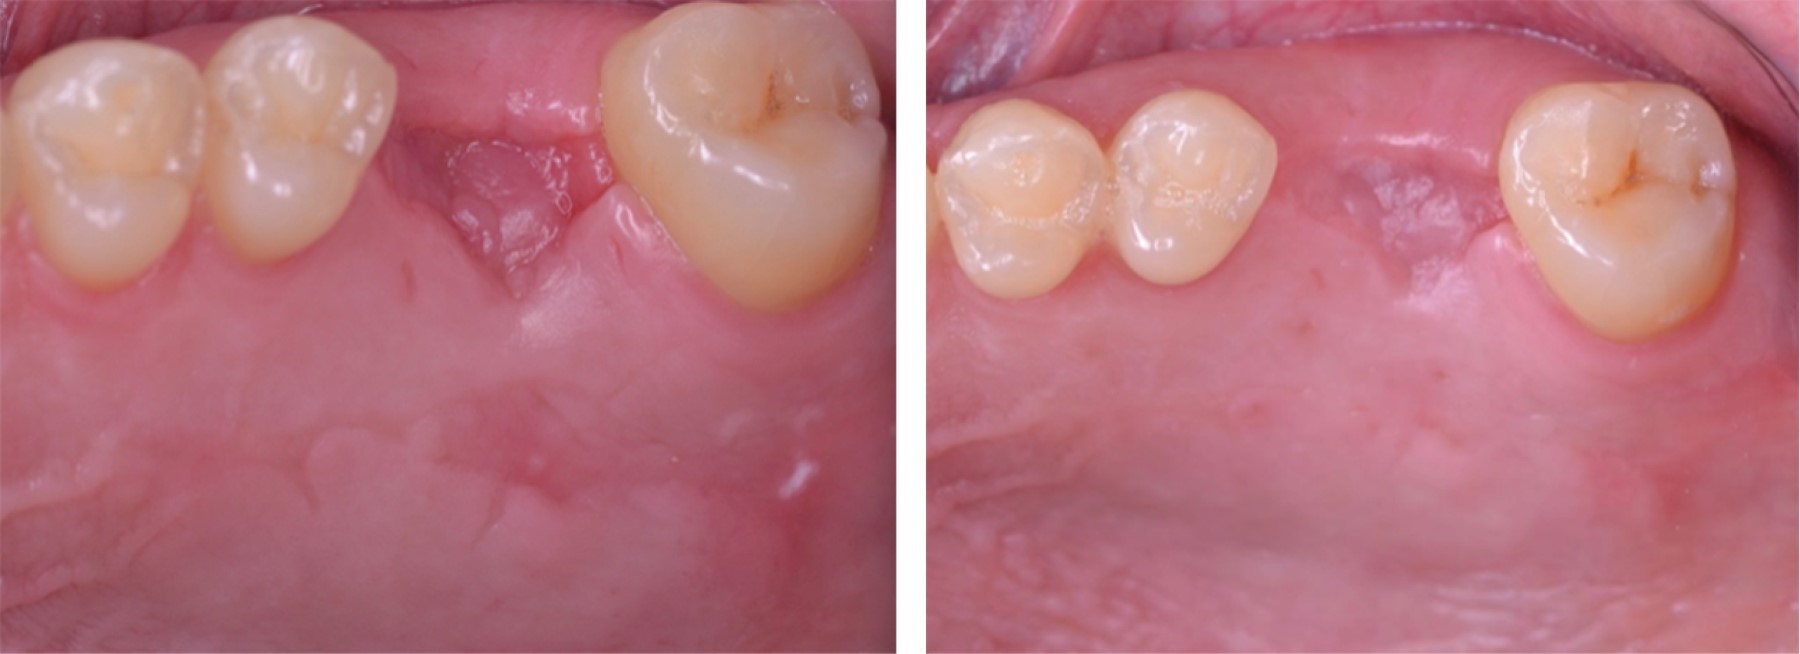

Al análisis radiográfico se observó dicho órgano dental con tratamiento de conductos y reconstrucción protésica y, al análisis tomográfico, se muestra un cuerpo radiopaco inusual dentro del seno paranasal derecho (Figura 2).

Se remitió al paciente a otorrinolaringología para la evaluación de dicho hallazgo. En la consulta, el médico especialista señaló como diagnóstico quiste de retención. El órgano dental se indica para extracción por fines protésicos, fractura dental y la presencia de dicho quiste.1 Se solicita autorización médica por escrito (la cual se otorgó por parte del otorrinolaringólogo) para poder realizar extracción, y se sugiere antibioticoterapia con quinolona, que en este caso fue levofloxacino de 750 mg por siete días antes de la intervención y siete días posteriores a ella.

Figura 2